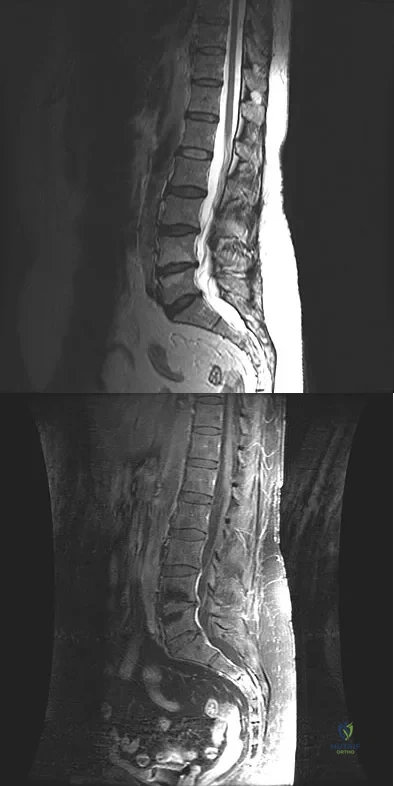

A 45-year-old man seen in the emergency department reports a 1-week history of worsening low back pain and a progressive neurologic deficit in the S1 distribution. Examination reveals 2/5 strength in the gastrocnemius. Laboratory studies show a WBC count of 13,500/mm3 and an erythrocyte sedimentation rate of 74 mm/h. Radiographs of the lumbosacral spine show narrowing of the L5-S1 disk space, with irregularity of the end plates. A sagittal T2-weighted MRI scan is shown in Figure 8. Definitive management should consist of

A 60-year-old woman with a history of breast cancer has progressive paraparesis. The MRI scan is shown in Figure 28. What form of management is most likely to restore or maintain ambulation?